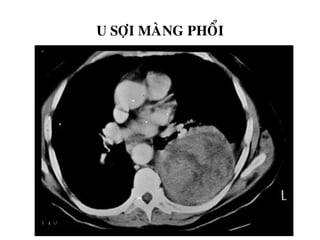

U SÔÏI MAØNG PHOÅI